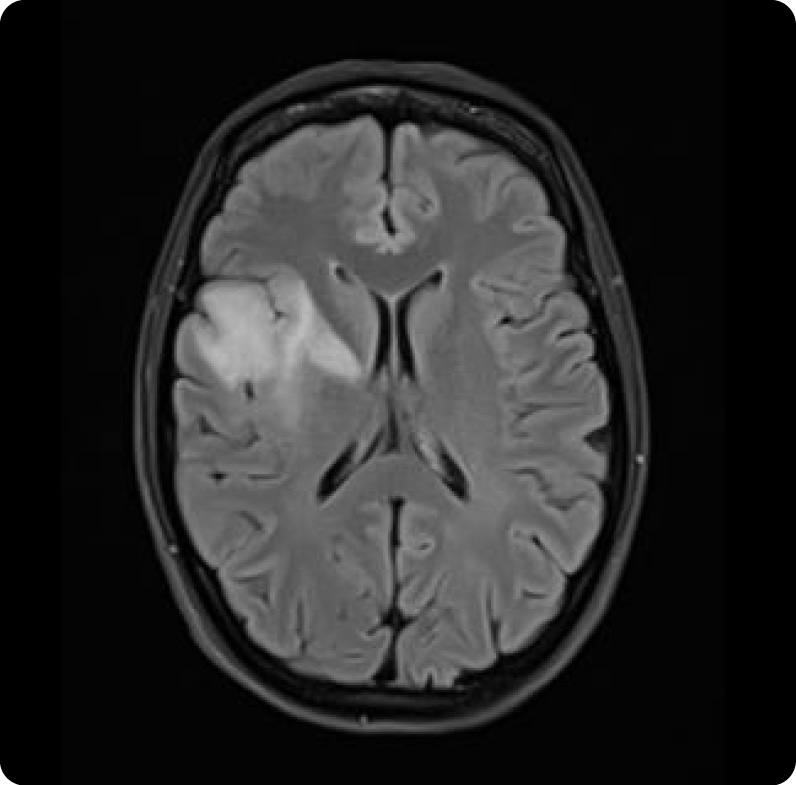

Scan of Luisa’s brain, showing her tumour.

Scans showed a Grade 2 oligodendroglioma sitting in a delicate area of her brain, dangerously close to the regions responsible for speech. Surgeons warned that operating could rob her of her ability to speak or cause irreversible brain injury. The only option they could offer was “watch and wait” – knowing she’d likely have no more than ten years to live.